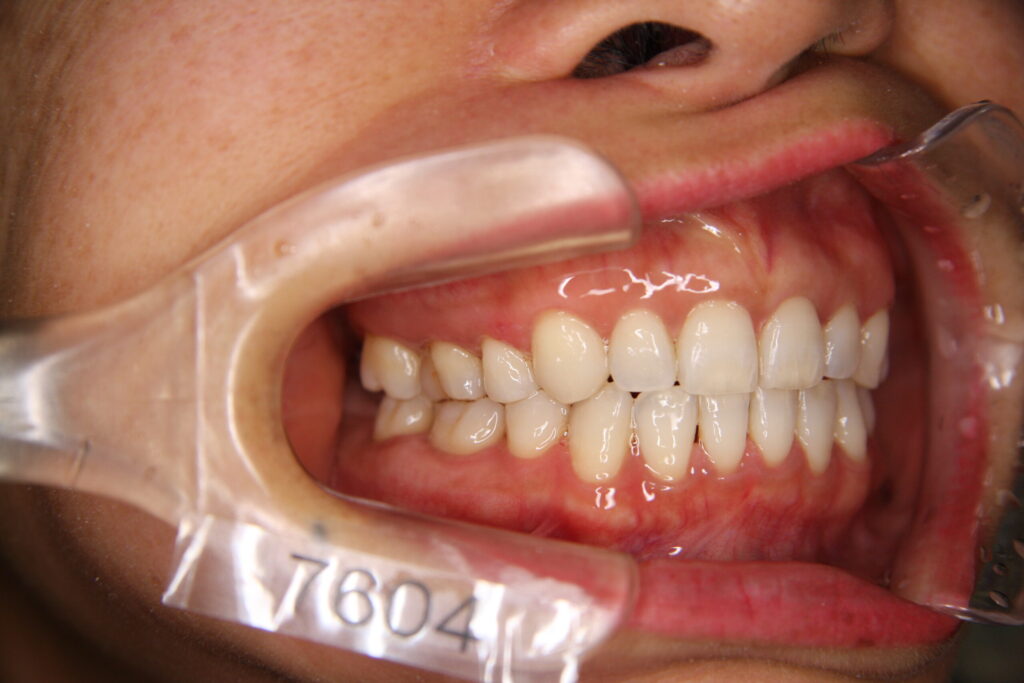

「カマクラデントフェイシャルオーソピディクスオリジナルの取り外しの効くミニマムアクチベータの治療結果」

「子どもの矯正歯科」 「日本歯科専門医機構認定矯正歯科専門医  山本一宏の blog 」 日本歯科専…